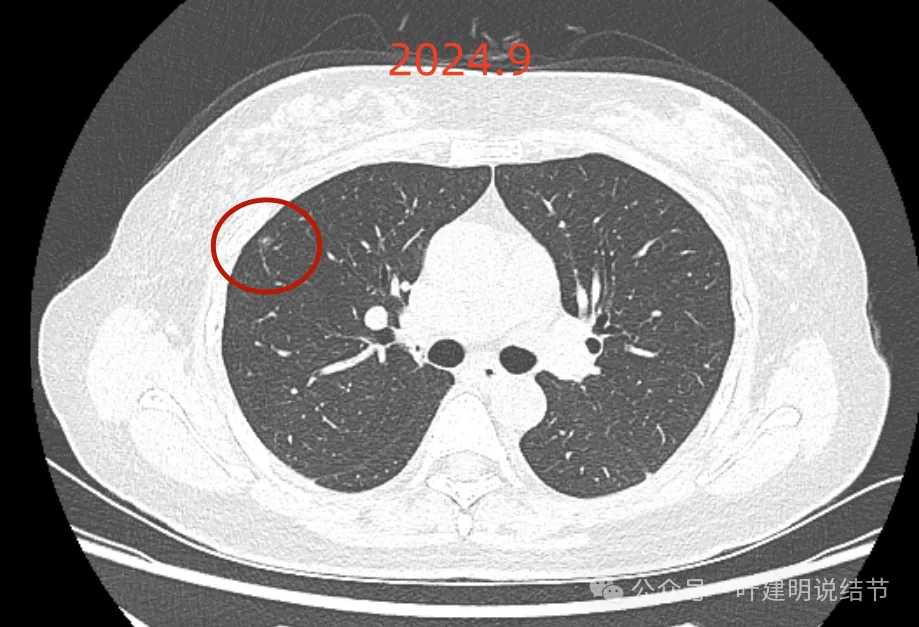

最后来看2024年9月,也就是叫停手术后2整年之后复查的情况:

仍说不上有明显进展,如果将这几次的放在一起来对照,就会更加直观:

病灶基本上没有明显变化。当然不必过于在意具体大小有没有几毫米的差别,也不必在意具体CT值有几十或百把的区别,微细的差别不影响临床决策,也就是说改变都不足以让肉眼发现的,怎么会影响预后呢!

我看了你2022年2月时的片子,以及某医院建议你手术说有进展时的2022年5月时的片子和2023年8月复查时的片子,再对比2024年9月时的影像,总体上明显点的病灶仍是这三处。首先均仍是纯磨,有的似有微血管进入或穿行,但磨玻璃成分密度很淡,而且大小无明显进展。至于右上病灶是否有缩小好转,感觉上右上的与右中叶的都略显淡了点,我怀疑还是扫描条件不一的关系,本身又是非常小而淡的病灶,可比性稍差,并不能说明必是有吸收好转。但肯定说不上有进展,风险仍是低的,半年或一年复查随访(个人倾向可以年度复查)总归不至于会耽误病情。意见供参考!